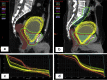

Methods and materials: This was a single institution retrospective study of 20 patients (390 CBCT scans) who received postprostatectomy RT. Each patient received a daily US before treatment. CBCT alignment was performed 3 times a week. The bladder and rectum were contoured on each CBCT and a session dose was recorded. A mixed-effect model was used to estimate trajectory slopes of radiation exposure with organs-at-risk volume increase. Slope differences by V40/65 for prostate fossa (PF) and pelvic lymph nodes (PF/pLN) were tested using a 3-way-interaction term with Bonferroni correction.

Results: For the 20 patients, 10 received treatment to PF and 10 received RT to the PF/pLN. Predefined bladder constraints were V65 < 50%, V40 < 70%, and rectal constraints were V65 < 35%, V40 < 55%. The CBCT bladder volume (76-578 cm3) was greater than the pretreatment bladder US (87-466 cm3) due to volume filling between measurements (r = 0.8 ± 0.05). Mixed model detected a statistically significant 3-way interaction (P < .01) for bladder volume and V40/65. Both PF and PF/pLN patients showed improvement in V40/65 with an increase in bladder volume. For PF patients, bladder constraints were met when the US volume was >108 cm3 and for PF/pLN patients when the US bladder volume was >200 cm3. Rectal filling showed no association with CBCT volume.